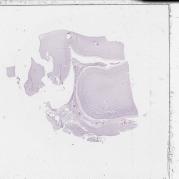

0-0-0.jpg